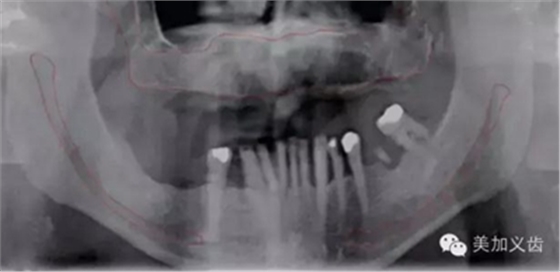

同時,曲面斷層片也存在缺陷,拍攝后的影像會有放大,或者存在扭曲和變形,此時測量的數(shù)據(jù)是不可靠的。曲面斷層片在拍攝時存在結(jié)構(gòu)重疊現(xiàn)象,因此會出現(xiàn)上頜竇粘膜的假陰性和假陽性病變,這也是其不準確的地方。

如何通過曲面斷層片測量出相對準確的數(shù)據(jù)?告訴大家一個很實用的方法,就是利用小剛球作為參照。

將小剛球放到口內(nèi)時拍攝曲面斷層片,拍攝后得到的結(jié)果就是這個樣子的:

因為小剛球的直徑是固定的,通過測量片子上小剛球的直徑,就能算出曲面斷層片的放大率,然后就能算出真實的骨高度了,這是一個很不錯的方法。